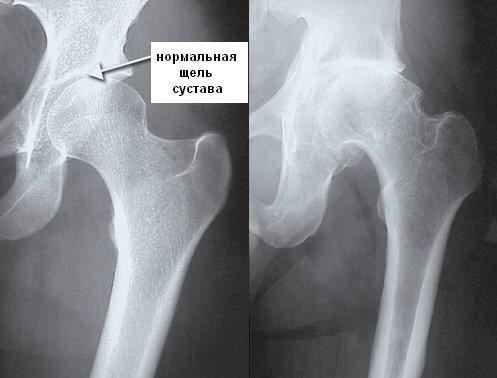

- Рентген пораженного участка. Позволяет увидеть, сужена ли щель в суставе пациента. Процедура показывает остеофиты и деформацию в зоне бедра;

Рентген-критериями коксартроза считаются уменьшение высоты суставной щели, уплотнение костной ткани в подхрящевой зоне, наличие костных разрастаний. Рентгенографическое сканирование проводится и левого, и правого сустава, что позволяет сравнить состояние.

Заболевание первой степени

Начальная стадия коксартроза приводит к небольшому сужению в суставной щели. В пораженной зоне разрушаются гиалиновые хрящи. Пациент ежедневно чувствует скованность и напряжение, особенно по утрам. Иногда возникает боль при активности и резких движениях. Слышится незначительный хруст в суставе.

Коксартроз второй степени

На данной стадии в области бедра появляются остеофиты. Может начаться подвывих суставной головки, и сузится щель. Пациент постоянно ощущает болевые приступы при движении. Начинаются сильные спазмы в мышцах. Если на данной стадии не начать лечение, тогда симптомы усугубятся и приведут к операции.

Болезнь третьей степени

Щель в суставе полностью исчезает и начинается большое давление на нервные окончания. Возникает очаг склероза в кости бедра. Вся подвижность сустава полностью пропадает. Болевые приступы начинаются не только при движении, но и в момент отдыха. Пациент уже не может давать опору на поврежденную зону. Одна нога становится короче другой.